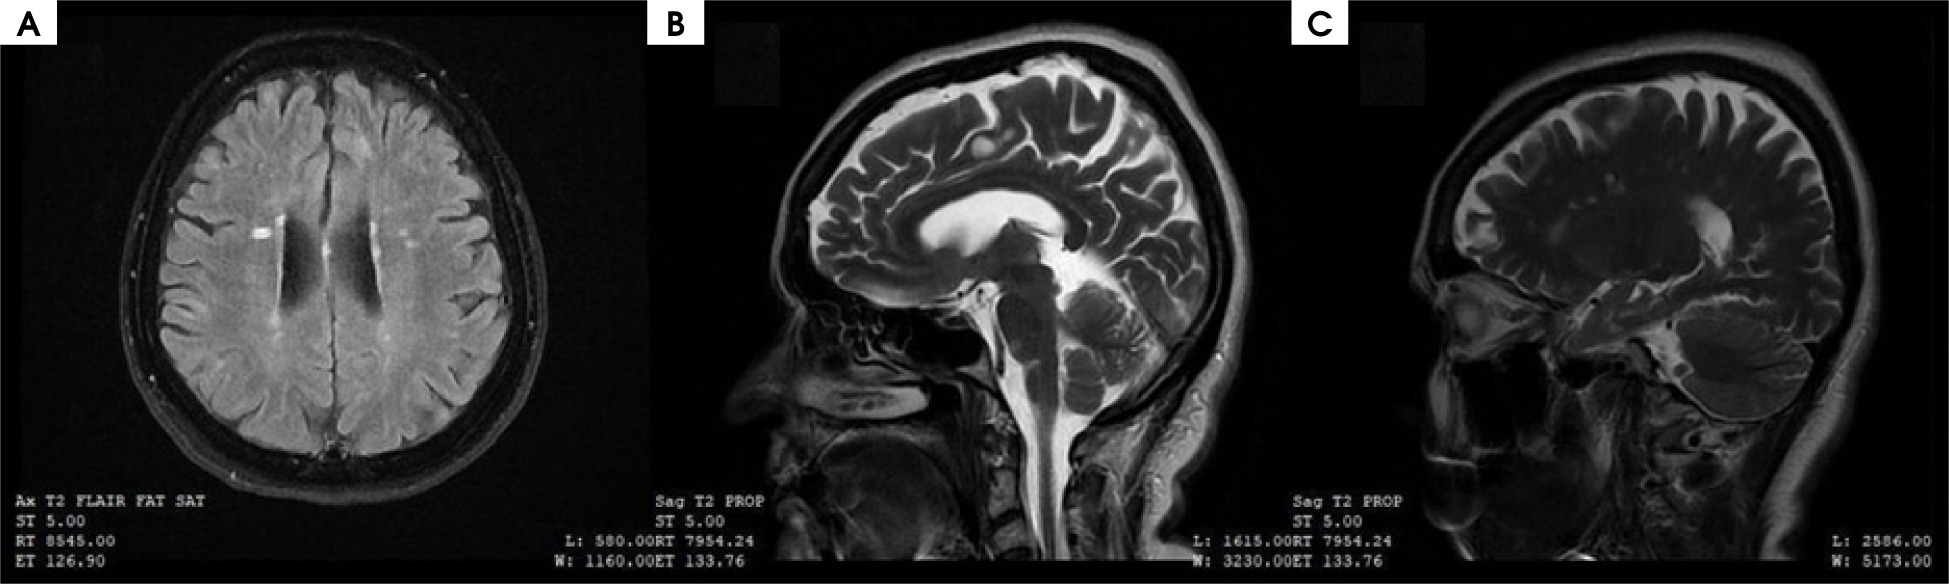

Figure I

A) Magnetic resonance imaging (MRI) scan of the brain in T2-weighted image in FLAIR sequence, (B) axial plane, (C) MRI scans of the brain in T2-weighted image, sagittal plane. Multiple sclerosis lesions according to Barkhof and Tintore MRI criteria for primary progressive multiple sclerosis [14]